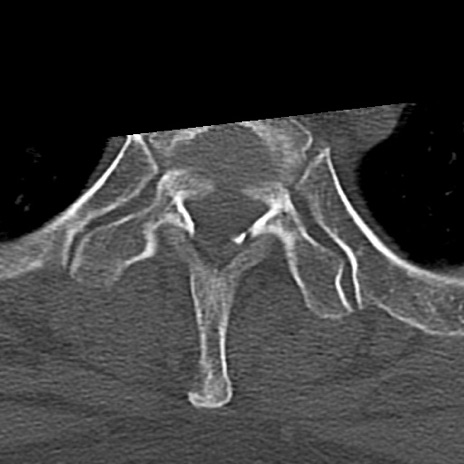

頚椎CT

横断像